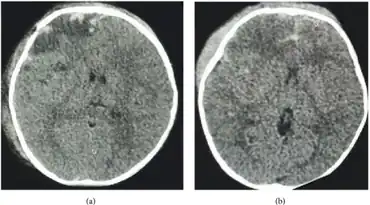

| Cerebral salt wasting syndrome following head injury in a child-image shows fracture of right frontal bone and subdural hematoma and extradural hematoma with contusion and subarachnoid hemorrhage | |